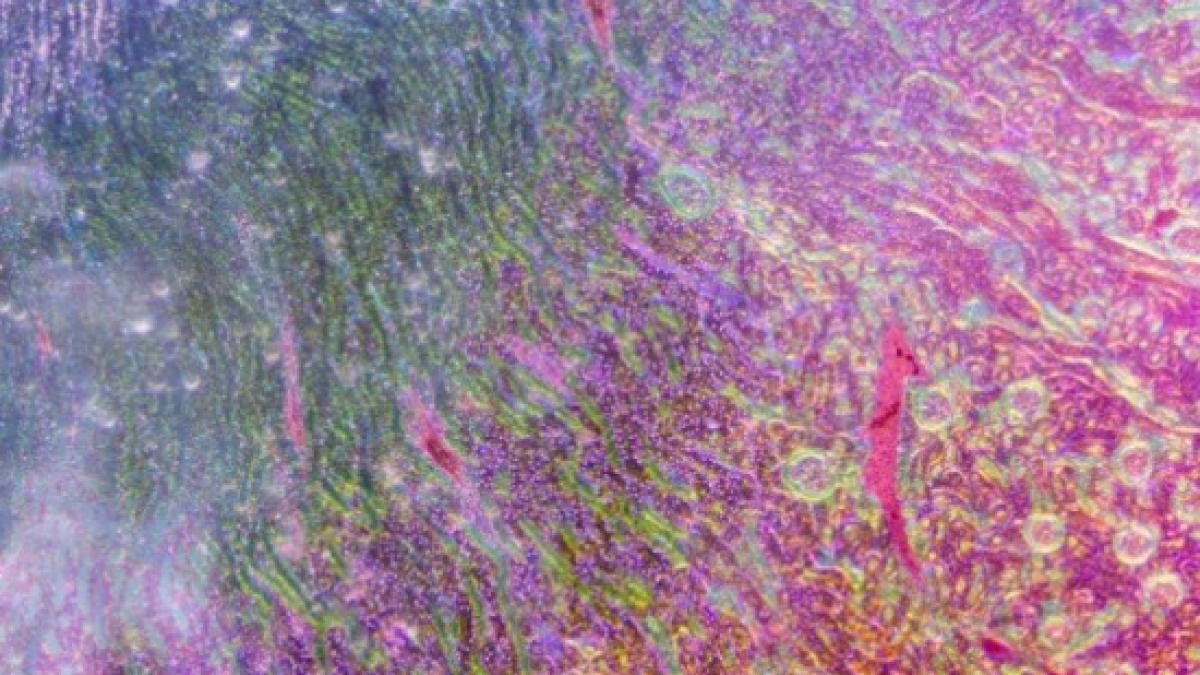

"Mugurii hepatici" au fost formati din celule stem, acestia fiind ulterior dezvoltati intr-un ficat uman. Dupa incheierea acestui proces, organul a fost grefat unui soarece.